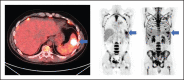

Our group has recently demonstrated that chimeric antigen receptor T-cell therapy targeting the CD30 antigen (CD30.CAR-T) is highly effective in patients with relapsed and refractory (r/r) classical Hodgkin lymphoma (cHL). Despite high rates of clinical response, relapses and progression were observed in a subset of patients. The objective of this study was to characterize clinical and correlative factors associated with progression-free survival (PFS) after CD30.CAR-T cell therapy. We evaluated correlatives in 27 patients with r/r cHL treated with lymphodepletion and CD30.CAR-T cells. With a median follow-up of 9.5 months, 17 patients (63%) progressed, with a median PFS of 352 days (95% confidence interval: 116-not reached), and 2 patients died (7%) with a median overall survival of not reached. High metabolic tumor volume (MTV, >60 mL) immediately before lymphodepletion and CD30.CAR-T cell infusion was associated with inferior PFS (log rank, P = .02), which persisted after adjusting for lymphodepletion and CAR-T dose (log rank, P = .01 and P = .006, respectively). In contrast, receiving bridging therapy, response to bridging therapy, CD30.CAR-T expansion/persistence, and percentage of CD3+PD-1+ lymphocytes over the first 6 weeks of therapy were not associated with differences in PFS. In summary, this study reports an association between high baseline MTV immediately before lymphodepletion and CD30.CAR-T cell infusion and worse PFS in patients with r/r cHL. This trial was registered at www.clinicaltrials.gov as #NCT02690545.